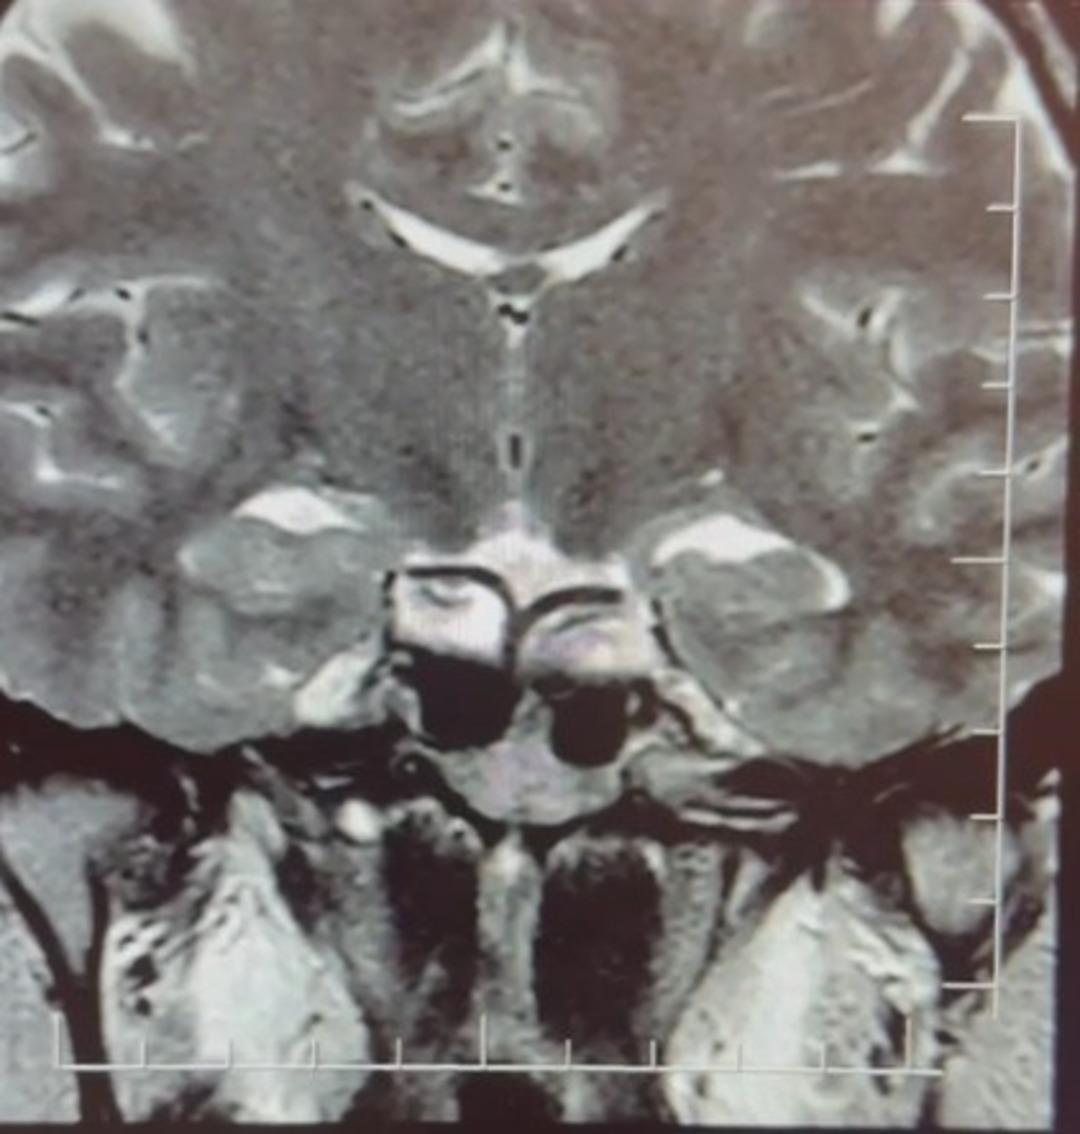

Yapılan ileri tetkiklerde hastaya hipofiz MR çekildiğini aktaran Çiftçoğlu, "MR sonucunda beynin hipofiz bölgesinde ‘prolaktinoma’ olarak adlandırılan bir tümör tespit ettik. Bu tümör, prolaktin hormonunun aşırı salgılanmasına neden oluyor. Genellikle iyi huylu olup ilaç tedavisiyle kontrol altına alınabiliyor" dedi.

Gebelik belirtilerine benzer şikayetlerin farklı hastalıkların habercisi olabileceğine dikkat çeken Çiftçoğlu, "Prolaktin hormonu aslında beyinde hipofiz bezinden salgılanan ve süt salınımını sağlayan hormondur. Bunun yüksek olduğunu tespit ettikten sonra hastada hipofiz MR çektirdik. Çektiğimiz beyin MR'ında hastanın hipofiz dediğimiz bölgede kitleyi tümörü tespit ettik. Prolaktinoma dediğimiz bir tümör. Prolaktinoma tümörü beyinde hipofiz bölgesinde bulunmakta olup prolaktin hormonunun aşırı miktarda salgılanmasını sağlayan bir tümördür. Bu durumda iyi huyludur, kanserleşme olasılığı çok yoktur. Dolayısıyla ilaçla tedavisi mümkündür ama gebelik şikayetlerini de andırdığı için mutlaka ayırıcı tanıda akılda tutulması gereken bir durumdur. Hasta da bizle öğrendi 'hamileyim' diye geldi hasta, gebelik muayenesi olma talebiyle geldi ancak biz tümörü tespit ettik. Önce gebe olmadığını tespit ettik ve sonra 'Bu şikayetlere sebep olabilecek ne var?' diye araştırdığımızda bu durum ortaya çıktı. Yani tümörü de aynı gün içerisinde değil birkaç gün sonra ileri tetkik sayesinde öğrenmiş oldu" dedi.